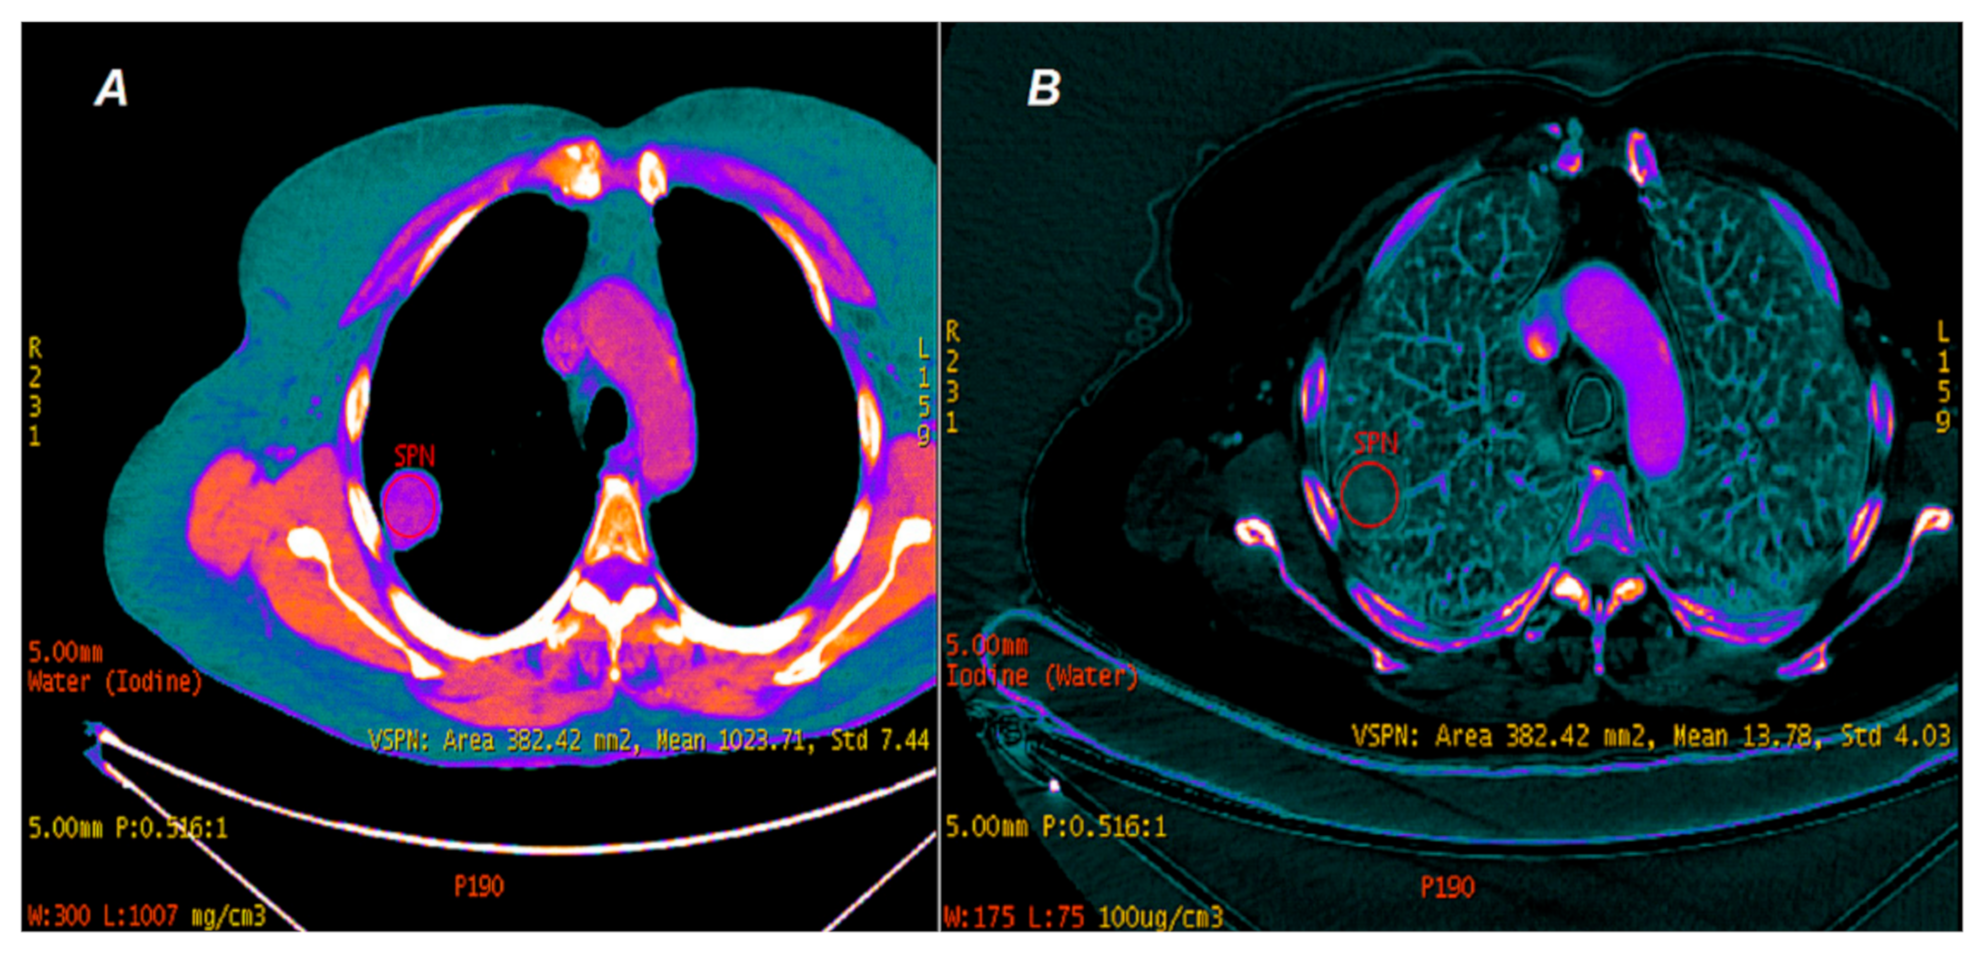

2. Materials and Methods

2.2. CT Scanning Parameters

2.3. Data Analyses

3.1.2. Comparison of Iodine Concentration in IC Maps, Water Concentration (WC) and Radiation Absorption in Lung Tumors in AP and VP of DECT Examination